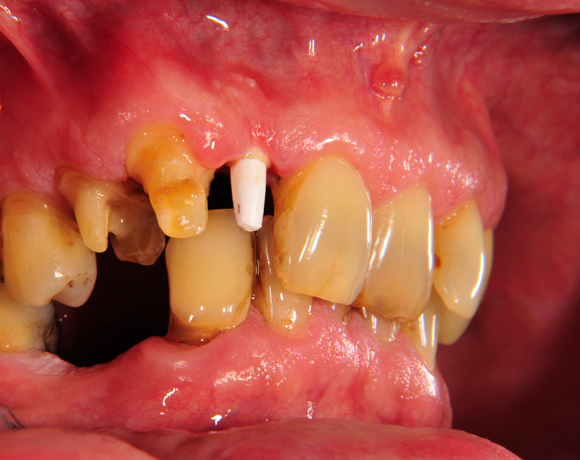

Vollkeramische Implantatkronen aus e.max lassen sich jederzeit mit vollkeramischen Kronen auf natürlichen Zähnen kombinieren ohne, dass ein Unterschied zu natürlichen Zähnen erkennbar ist.

Bei diesem Patienten wurde der nichterhaltungswürdige Zahn 12 mit einem Zerameximplantat versorgt. Nach der Einheilphase wurden auch die Zähne 14 und 13 mit e.max Kronen versorgt